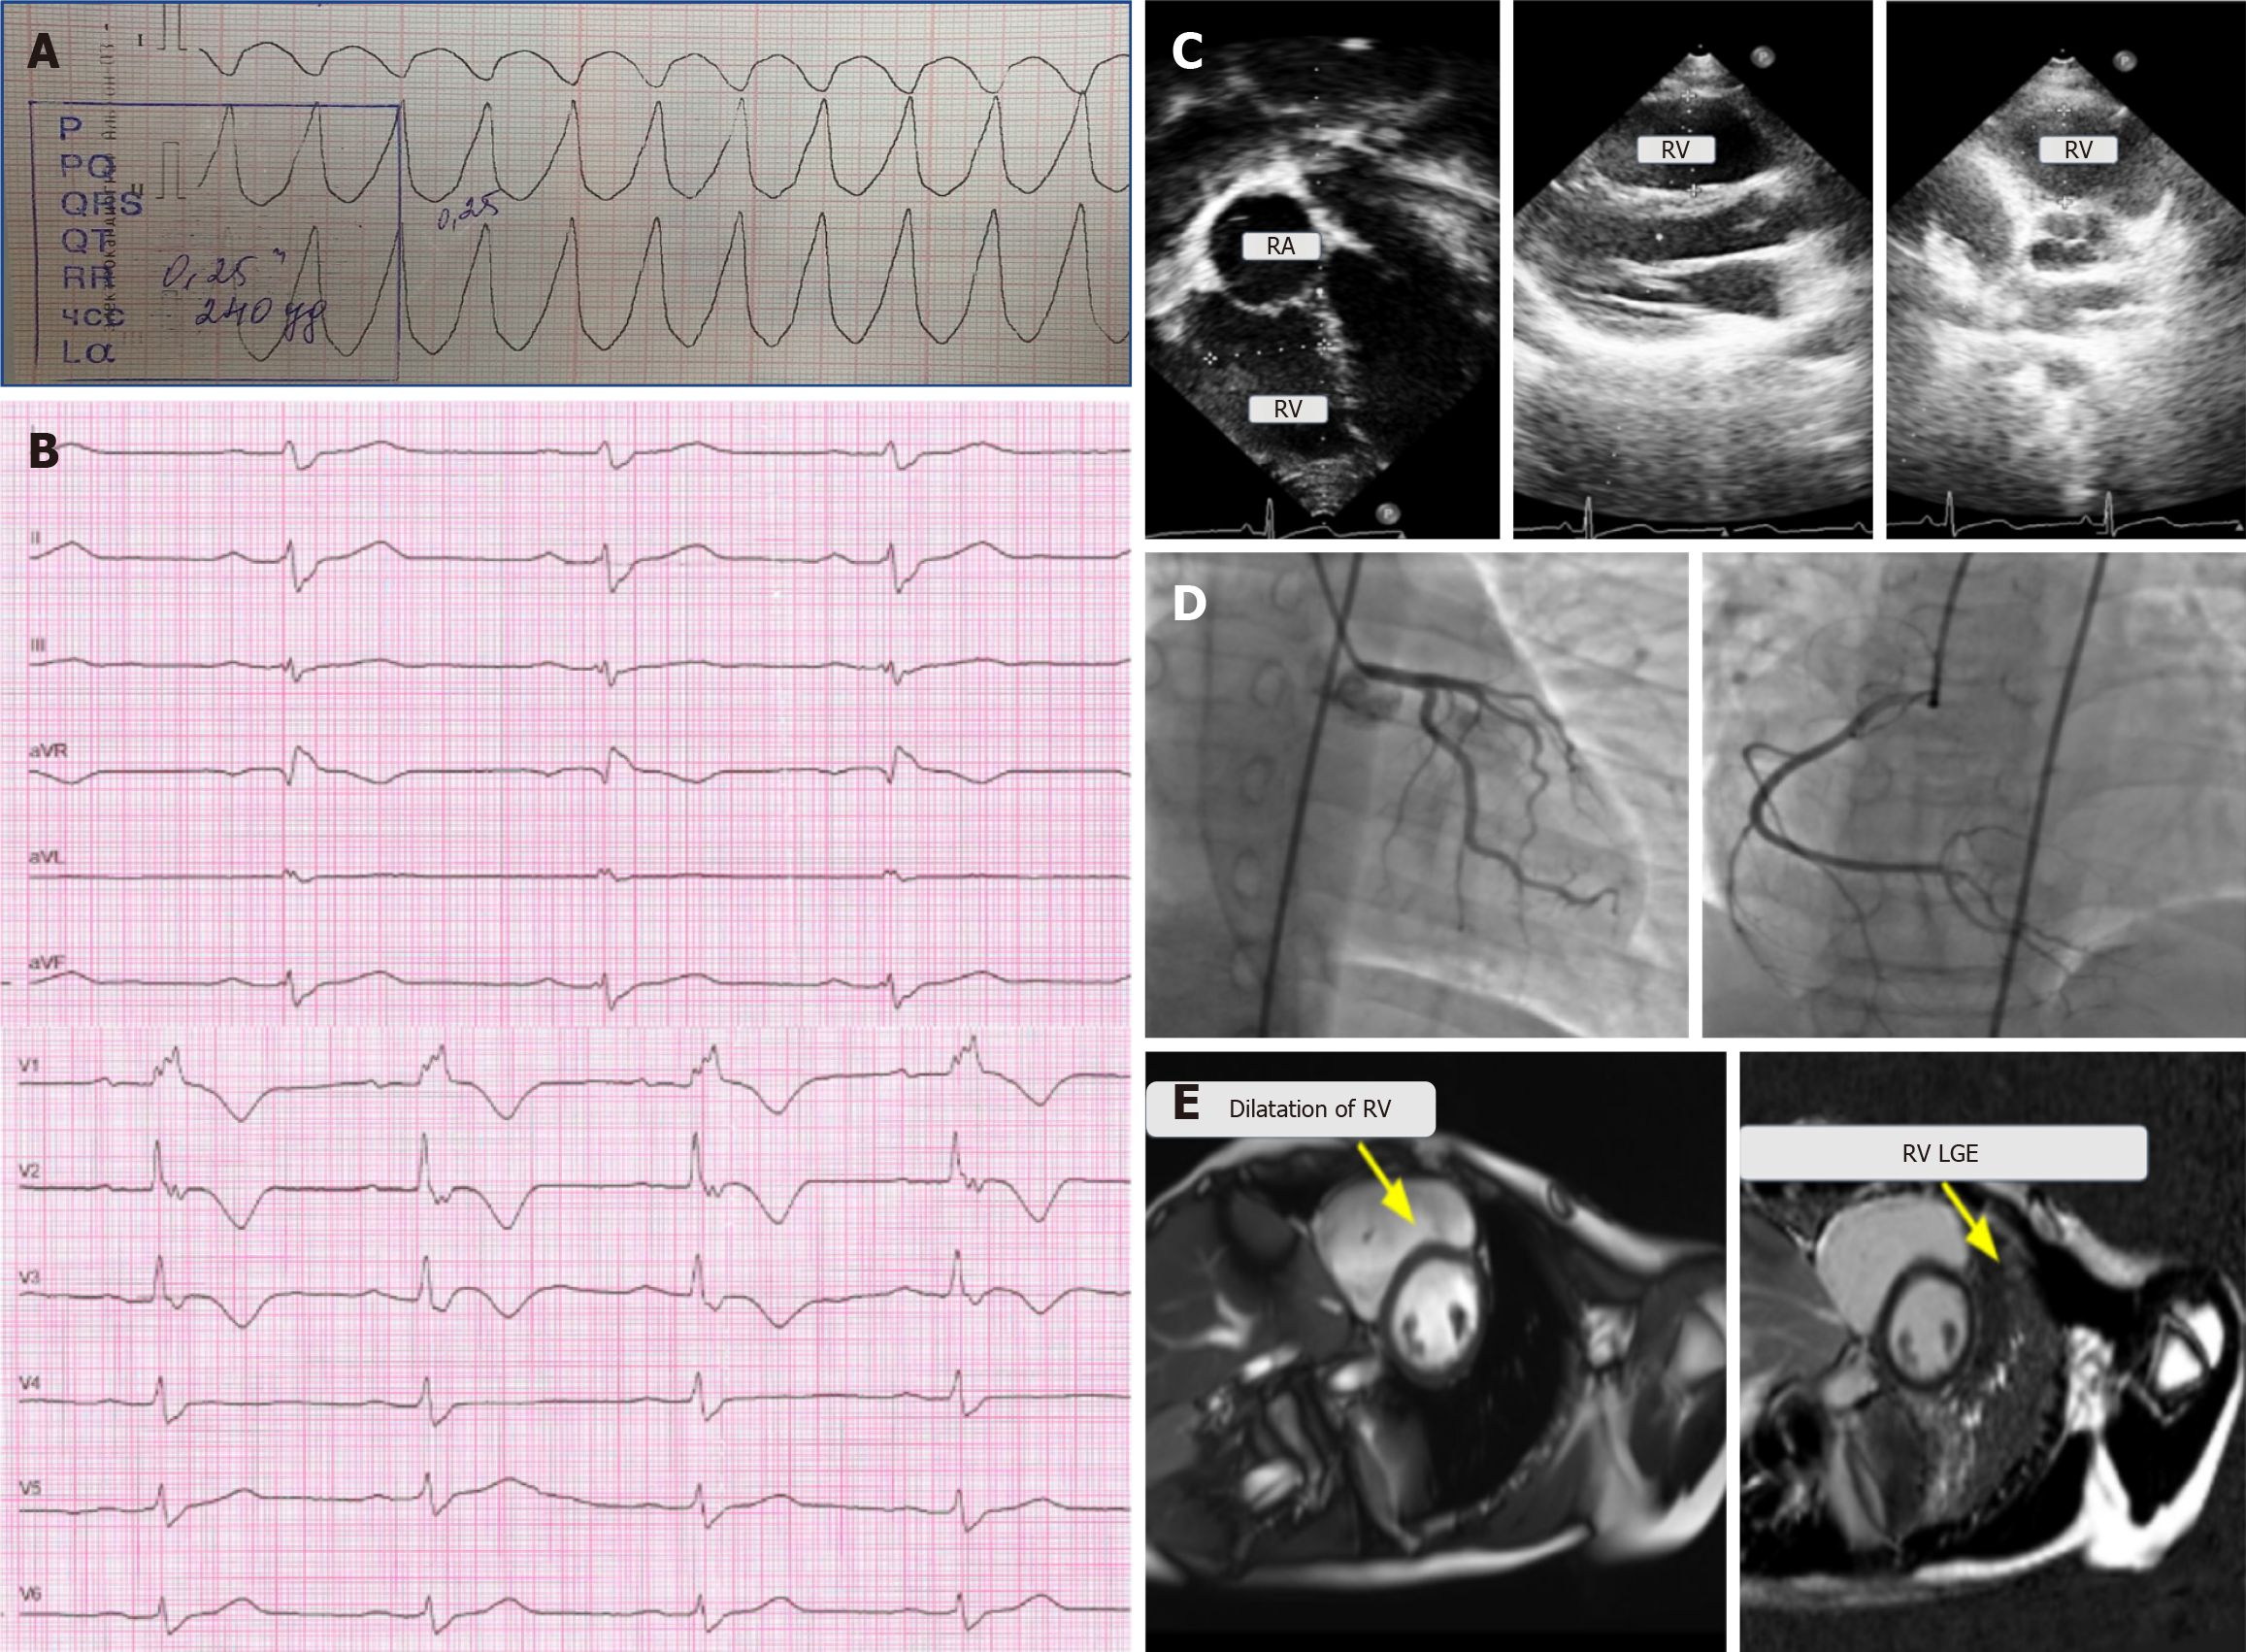

Figure 1 Electrocardiography, echocardiography, angiography, and cardiac magnetic resonance imaging of a 13-year-old boy with a single episode of syncope and ventricular tachycardia.

A: Electrocardiography (ECG) fragment with wide complex QRS tachycardia and a heart rate of 250 per minute; B: ECG during chest pain, sinus rhythm with a heart rate of 64 bpm, and right bundle branch block; C: Echocardiography—right ventricle dilation in the four-chamber position and parasternal position in the long and short axes; D: Type of coronary blood supply—right, coronary arteries with no angiographic signs of atherosclerotic lesions, no local stenosis, and satisfactory blood flow; E: Cardiac magnetic resonance imaging—right ventricular (RV) dilation and late gadolinium enhancement in the RV myocardium. RA: Right atrial; RV: Right ventricular; LGE: Late gadolinium enhancement.